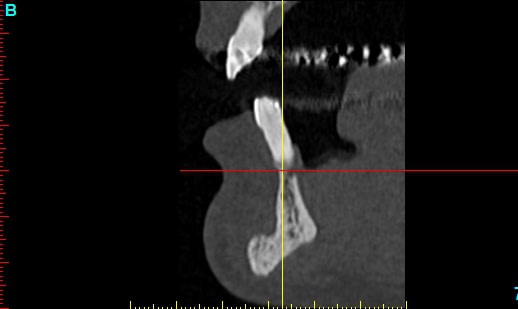

Patiente 58 ans à eu une chirurgie à visée esthétique et "fonctionnelle" adressée pour détartrage en urgence...je ne suis pas spécialiste mais je trouve que la greffe mentonnière est très bof

lésion apicale sur 42 risque de contamination sur la vis en regard..

j'ai demandé un scan en urgence.

Nous sommes d'accord pour la chirurgie mais secteur 4 il y a 2mm être là plastie et la mdble, ça ne me fais pas rêver

La chirurgie à 6 mois

Nous sommes d'accord pour la genioplastie je me suis mal exprimé ce qui m'inquiète c'est la proximité de la greffe, pardon genioplastie et de l'infection de 42, d'une part et la mauvaise liaison de la genioplastie secteur 4, mais je suis peut-être pessimiste.

Plusieurs points: les vis de 15mm x 2mm qui transfixent c'est pas top, une seule plaque, qui plus est non réglable de chaque côté, c'est encore moins top. C'est une plaque de fracture.

En mandibulaire gauche c'est quoi ce fil d'osteosynthese? Un troisième fragment? En laissant l'apex de la 48 pile sur le trait d'osteotomie, je dis chapeau.

Pour la lésion de 42, ca peut être lié à la genio. Forage hasardeux? Mais je vote plus pour une lésion endo/paro